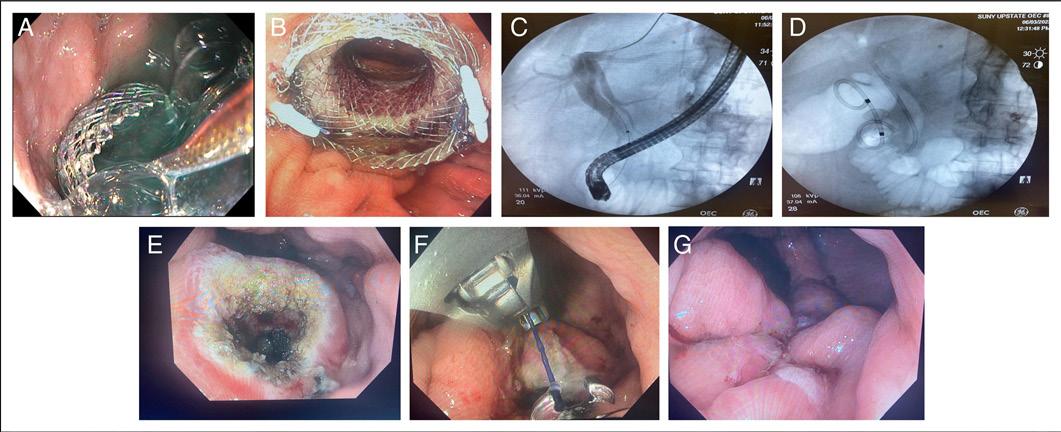

40 ACGCRJ

Introducing the 2024-2025 ACGCRJ Editorial Board and a case by Hussain, et al., with an accompanying podcast